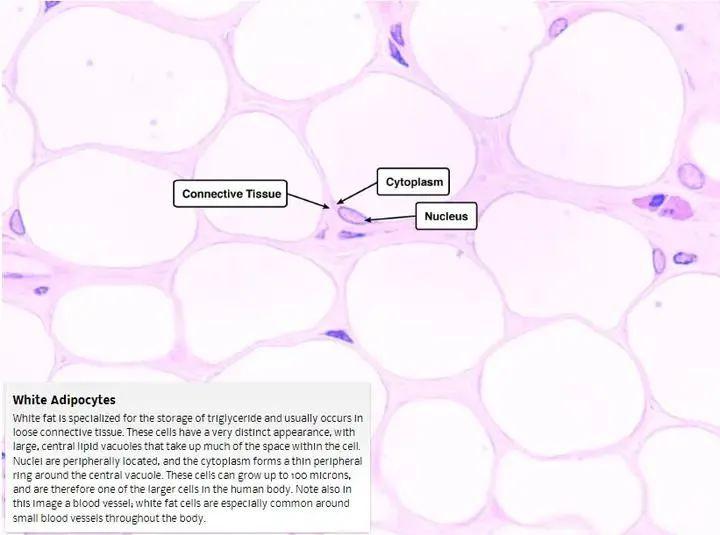

每個白色脂肪細胞裏只裝着一滴脂肪。

白色脂肪

白色脂肪,其實不僅僅是個“油罐子”,它還有一些隱藏技能哦!

它除了幫你囤熱量,它還會分泌一種叫脂聯素的激素,這玩意兒特別給力,能讓你的肌肉和肝臟對胰島素更加敏感,這樣身體裏的糖分就能被有效利用。

不僅如此,白色脂肪還會抑制你的食慾,發信號提醒你要停止進食了!

不過,白色脂肪有個“致命缺點”,要是你存太多白色脂肪,它就開始“罷工”了,直接導致脂聯素的產量大打折扣。